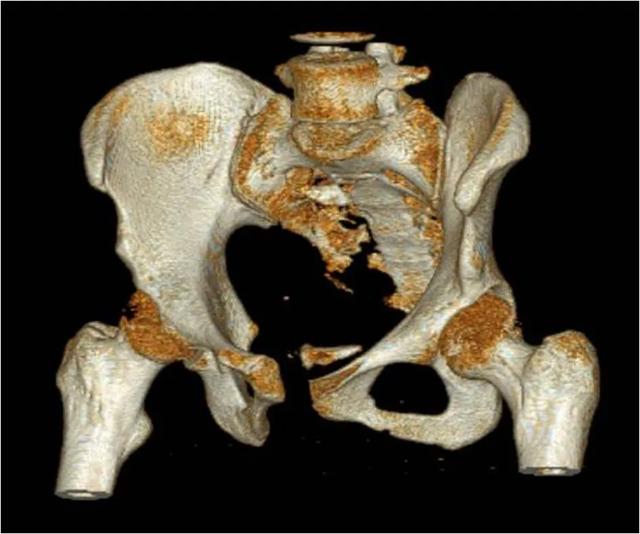

En orthopédie, il existe également des procédures plus traumatisantes, telles que l'opération de l'art orthopédique.颈椎de la chirurgie, ainsi qu'à lafracture du bassinde la chirurgie, etc.

Si tout le monde connaît l'importance de la colonne cervicale, vous ne savez peut-être pas grand-chose du bassin.Les saignements dus à une fracture du bassin sont particulièrement abondantsC'est pourquoi les chirurgiens orthopédistes procéderont toujours à une évaluation systématique du patient avant d'opérer un traumatisme majeur, tout en disposant de sang en réserve pour faire face à l'éventualité d'une hémorragie au cours de l'opération.

- fig. dépenser de l'argentLe tissu osseux est richement hématogène, en particulier dans les sections osseuses, les cavités de la moelle osseuse ou le canal rachidien, et les saignements sont généralement importants et difficiles à contrôler. Certaines des procédures les plus invasives, telles queLes saignements seront plus élevés en cas d'arthroplastie totale de la hanche, de chirurgie rachidienne et de chirurgie pelvienne.. Si l'hémorragie peropératoire est importante, un choc hémorragique peut se produire. Bien qu'une transfusion sanguine peropératoire soit possible, une perte de sang importante peut toujours être physiquement intolérable pour les personnes âgées dont la fonction cardio-pulmonaire est faible.